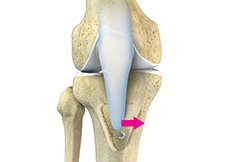

High Tibial Osteotomy

Knee osteotomy is a surgical procedure in which the upper shinbone (tibia) or lower thighbone (femur) is cut and realigned. It is usually performed in arthritic conditions affecting only one side of your knee and the aim is to take pressure off the damaged area and shift it to the other side of your knee with healthy cartilage.